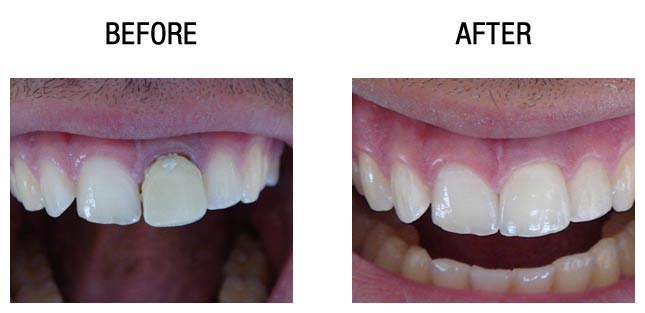

种植牙前后对比

种植牙前后对比